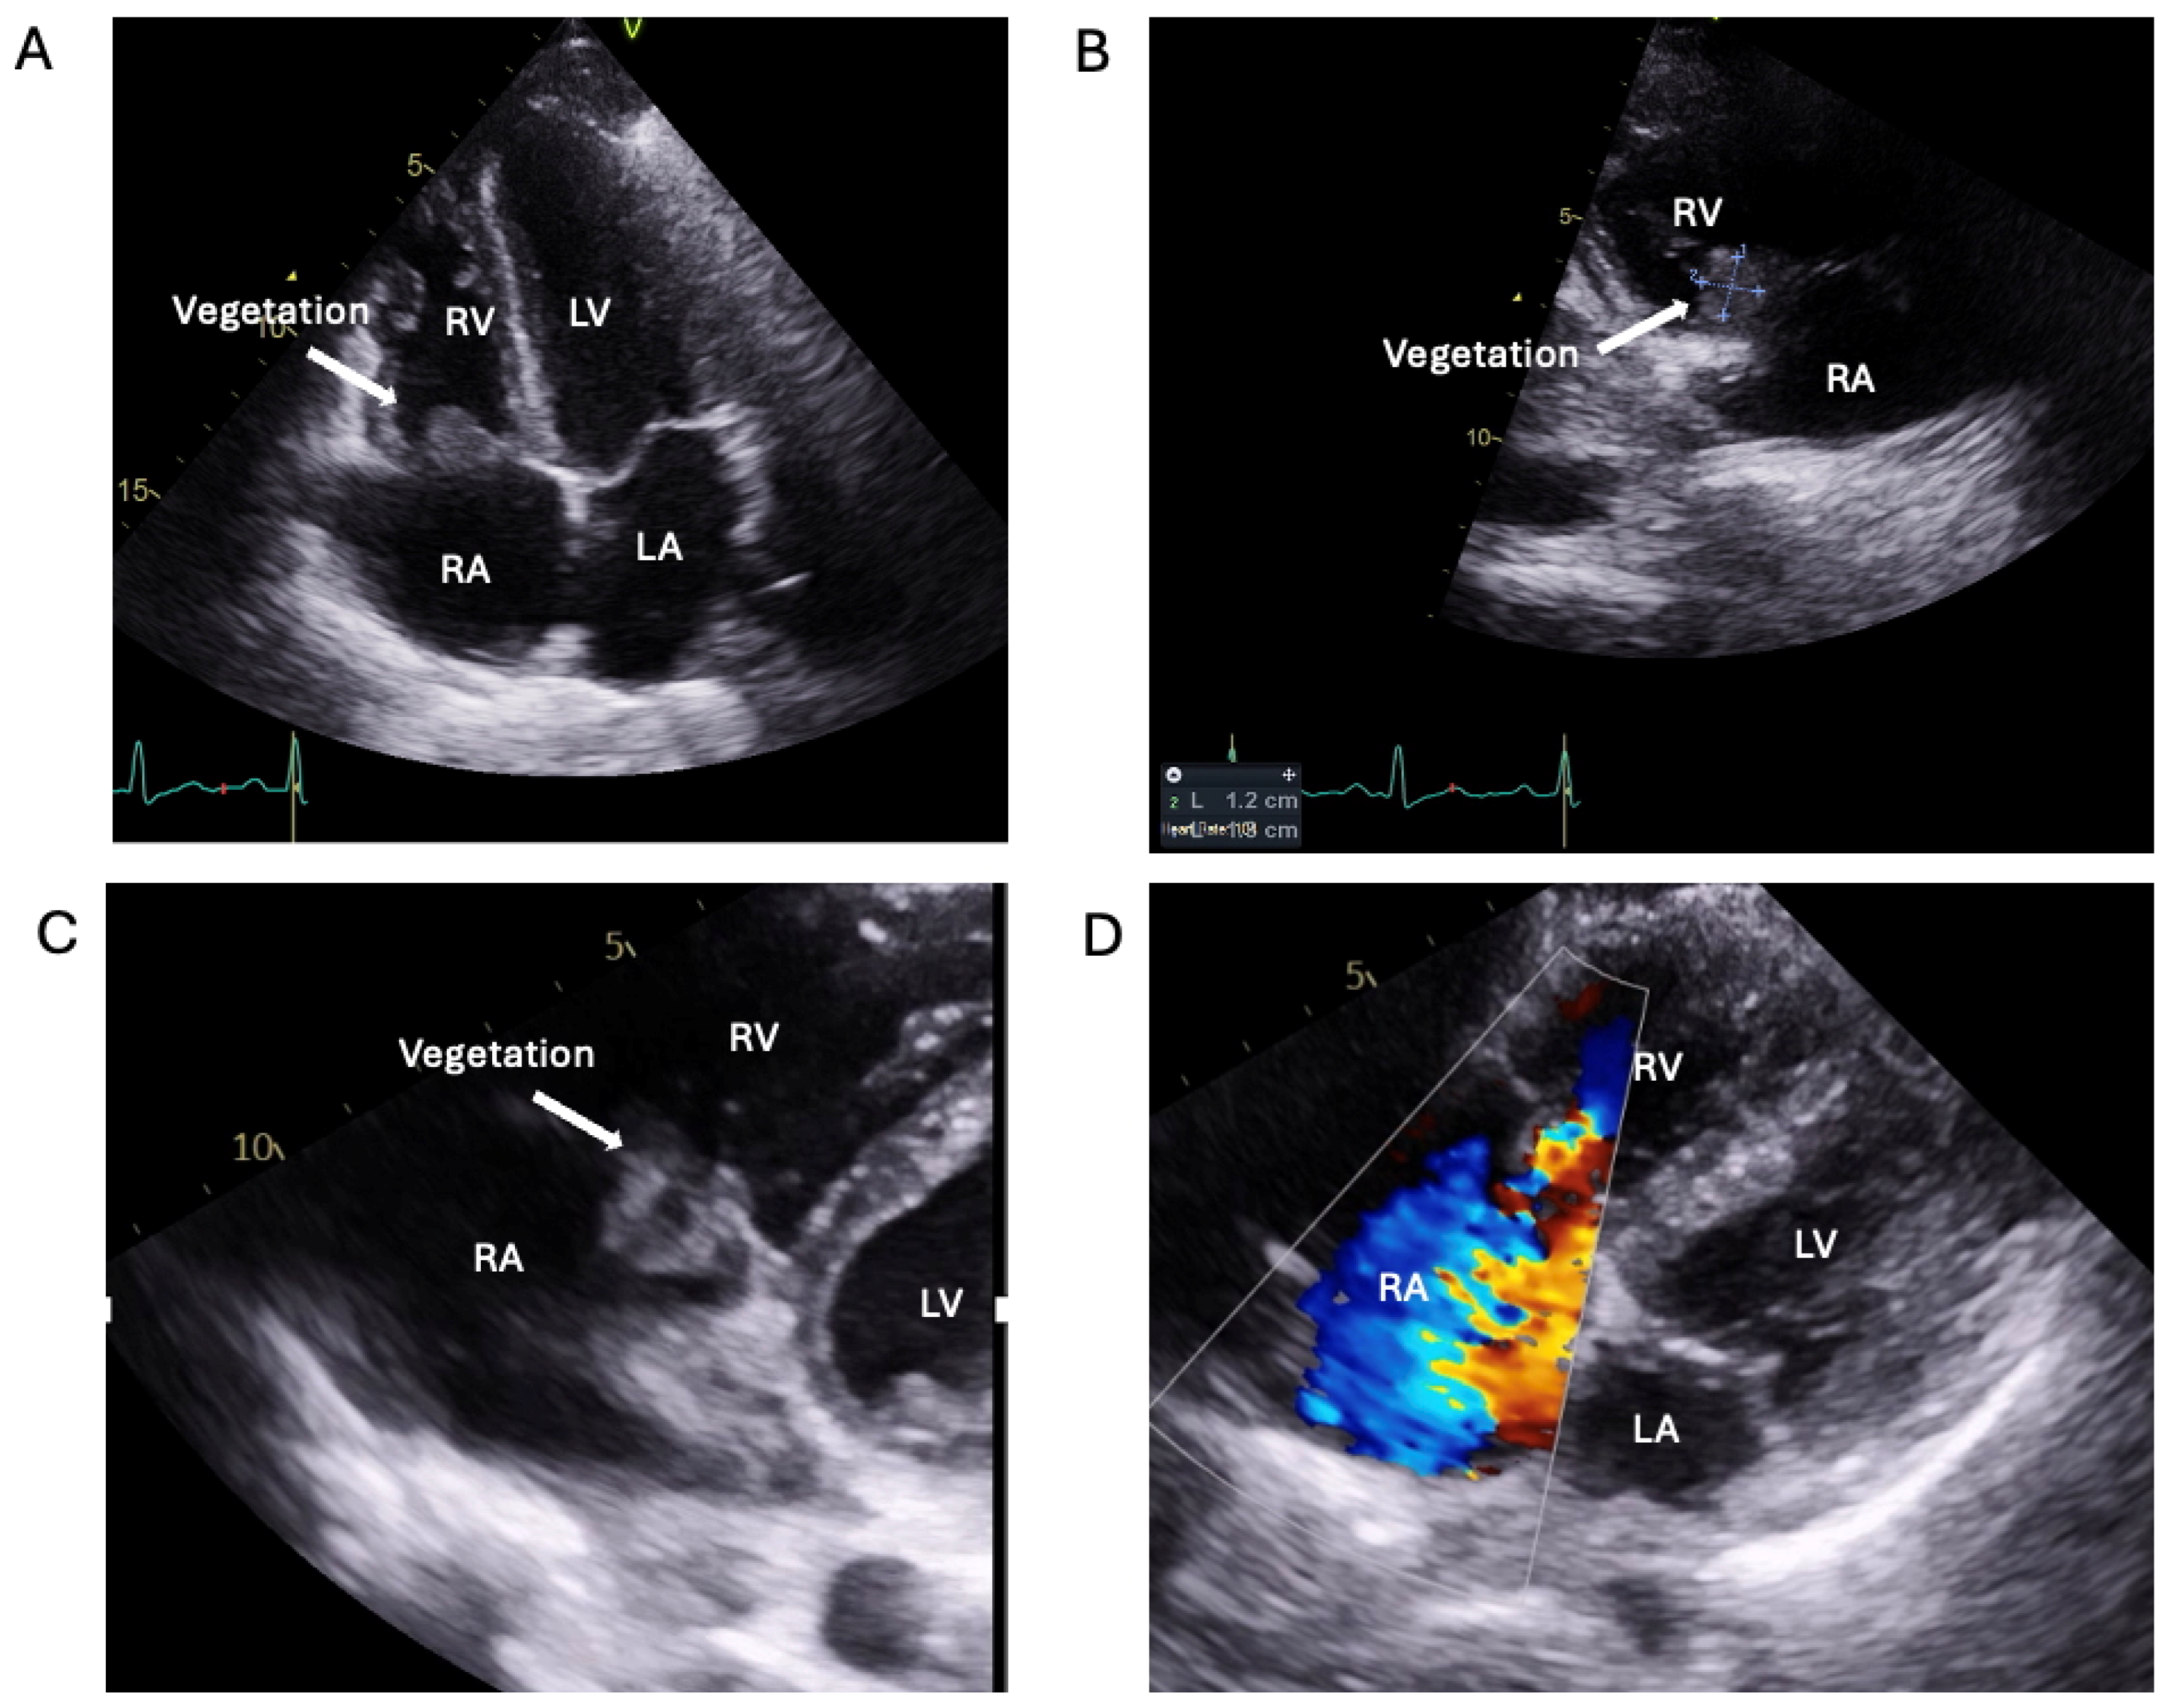

1.1.2. Case 2

2.2. Logistical Management Challenges in a Non-Compliant High-Risk Young PWID with Relapsing Right-Sided IE